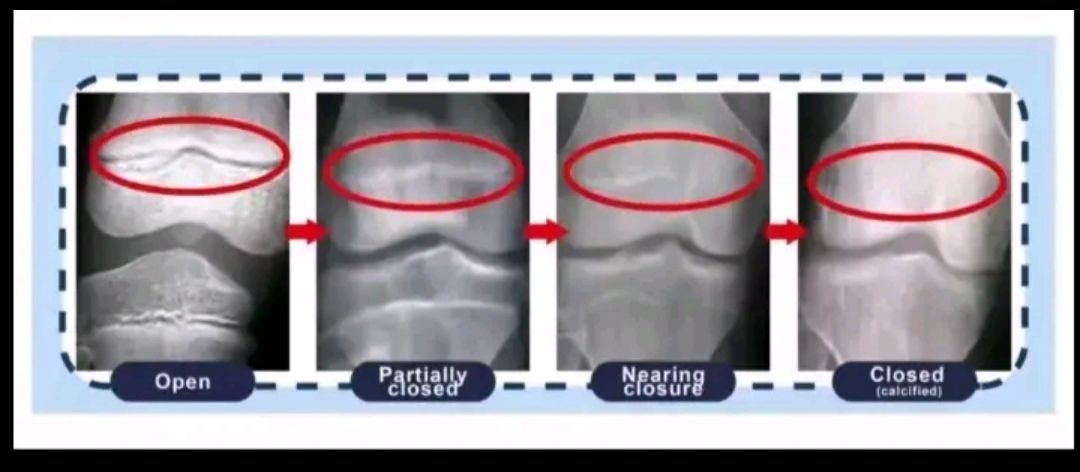

How oldAre my growth plates open and what is my bone age,

X-rays are general knee injury X-rays, not the best for evaluating this but if anyone knows

not fully closed but nearlyAre my growth plates open and what is my bone age,

X-rays are general knee injury X-rays, not the best for evaluating this but if anyone knows

eh maybe you have some timenot fully closed but nearly View attachment 4792713